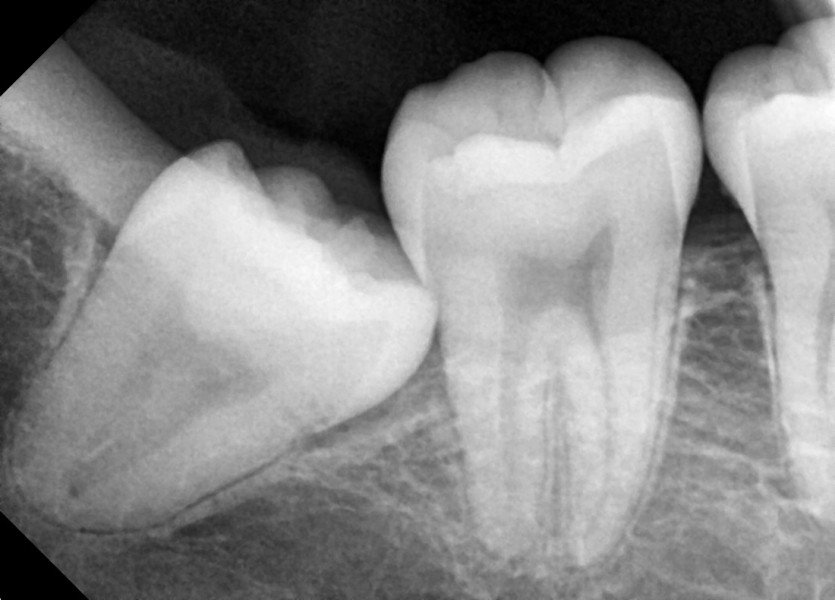

#38,48 사랑니 발치

구강 외과 전문의가 당일 발치했습니다.